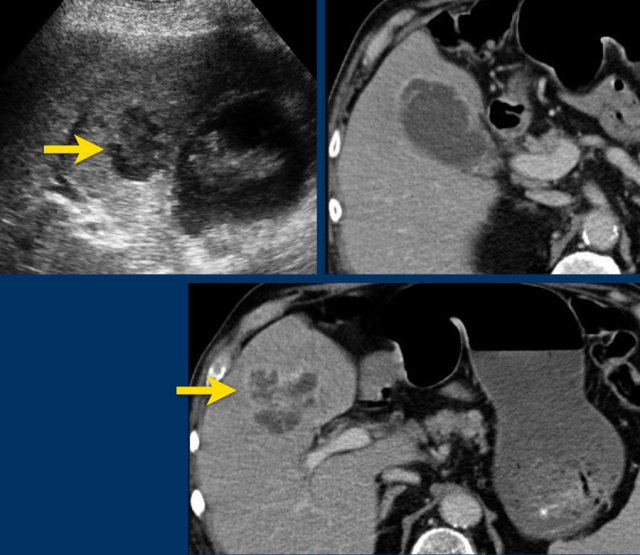

Abscess in the liver adjacent to the gallbladder in acute cholecystitis, visible on both US and CT.

Percutaneous drainage of the gallbladder was done.

The abscess drained itself into the gallbladder lumen.